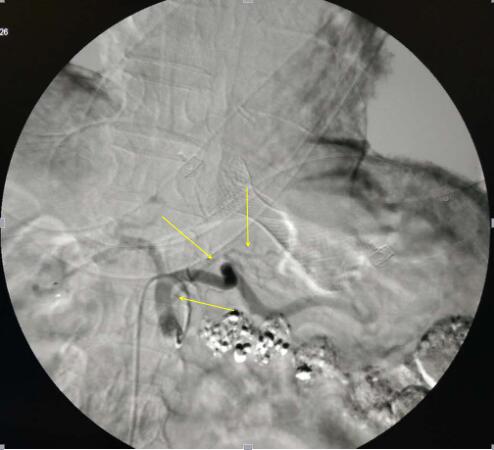

经皮选择性腹腔干造影

(黄色箭头所指为肿瘤主要供血动脉)